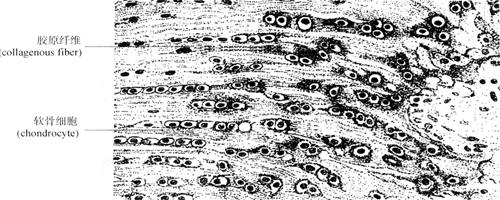

3.纤维软骨(fibrocartilage) 主要分布于椎间盘的纤维环、耻骨联合以及某些肌腱和韧带附着于骨的部位等处。主要特点是含大量平行或交叉排列的胶原纤维束,软骨细胞排列在纤维之间(图2-34)。

图2-34 纤维软骨模式图